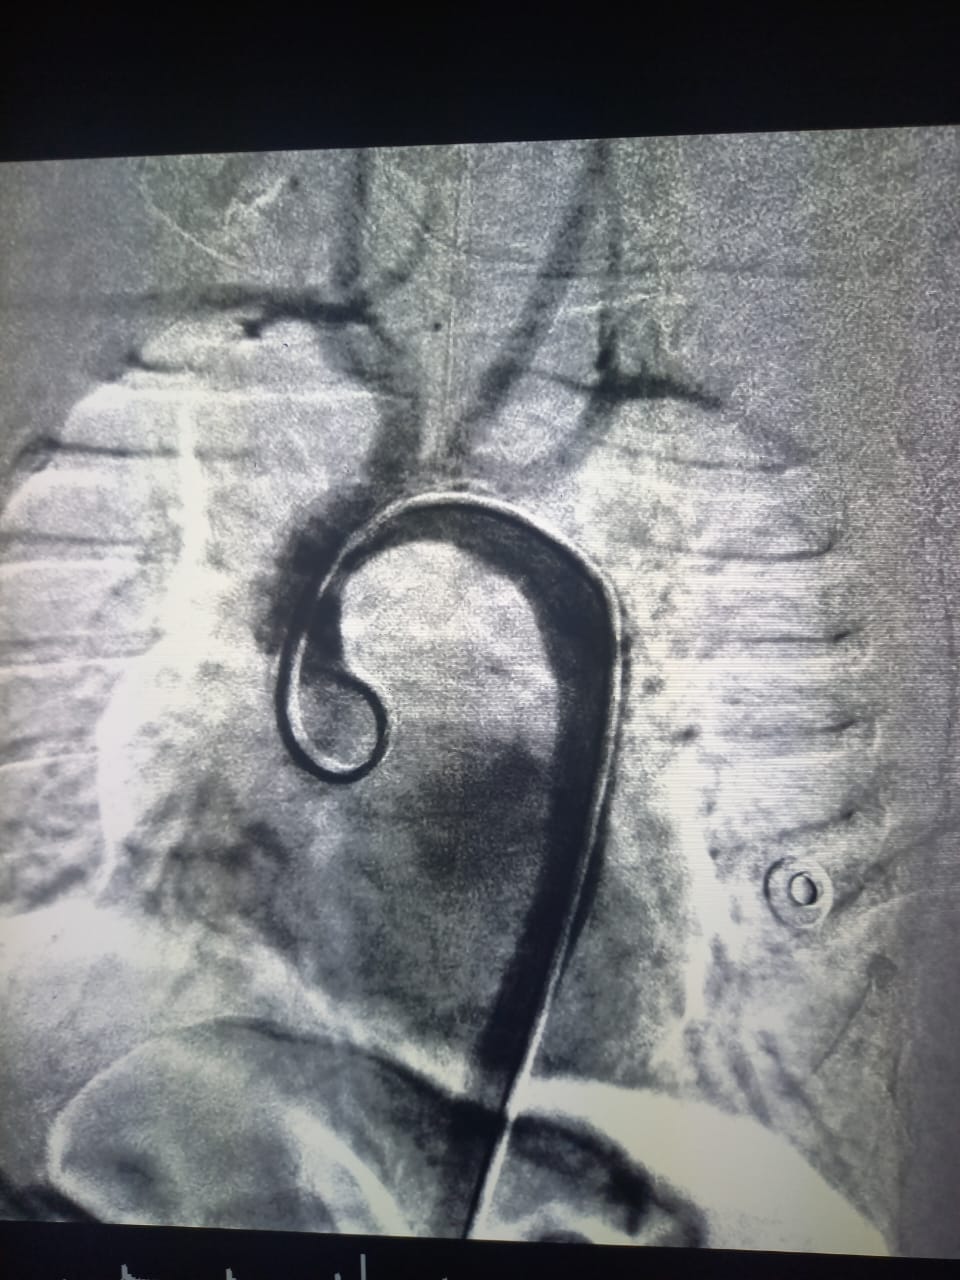

Специалистами НКЦКТ 1,5 мес младенцу проведена операция (под рентген контролем) при врожденном пороке сердца: рентгенэндоваскулярная ангипопластика Коарктации аорты.

Проведено полное диагностическое обследование: ЭхоКГ, КТ сердца с контрастированием. Был установлен Диагноз: ВПС Коарктация аорты Гипоплазия дуги аорты, сердечная недостаточность 3 ст. Снижение фракции выброса левого желудочка до 30%.

Ребенок госпитализирован в НКЦКТ. Консилиум в составе: профессора Джошибаева Сейтхана, зав. ДХКО Мухамедова Икрома, зав. ОРИТ Розбаева Зафара, зав. РЭХ Сейсембекова Вадима и врачей НКЦКТ кардиохирурга Кенбаева Азамата, детского кардиолога Уколовой Юлии, врача неонатолога Есенкуловой Аиды, учитывая низкую фракцию левого желудочка проведение открытой операции представлял высокий риск для ребенка, решено выполнить транслюминальную баллонную ангиопластику Коарктации аорты. Операция прошла благополучно, с хорошим гемодинамическим эффектом (без градиента).